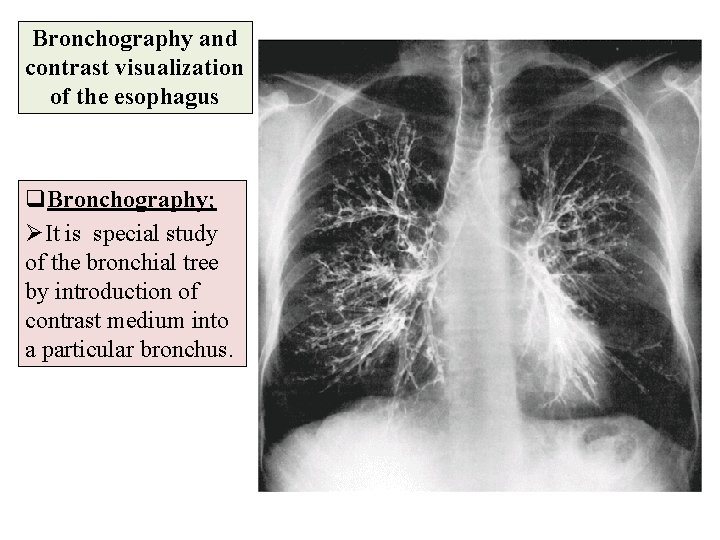

Bronchography and contrast visualization of the esophagus q. Bronchography; ØIt is special study of the bronchial tree by introduction of contrast medium into a particular bronchus.